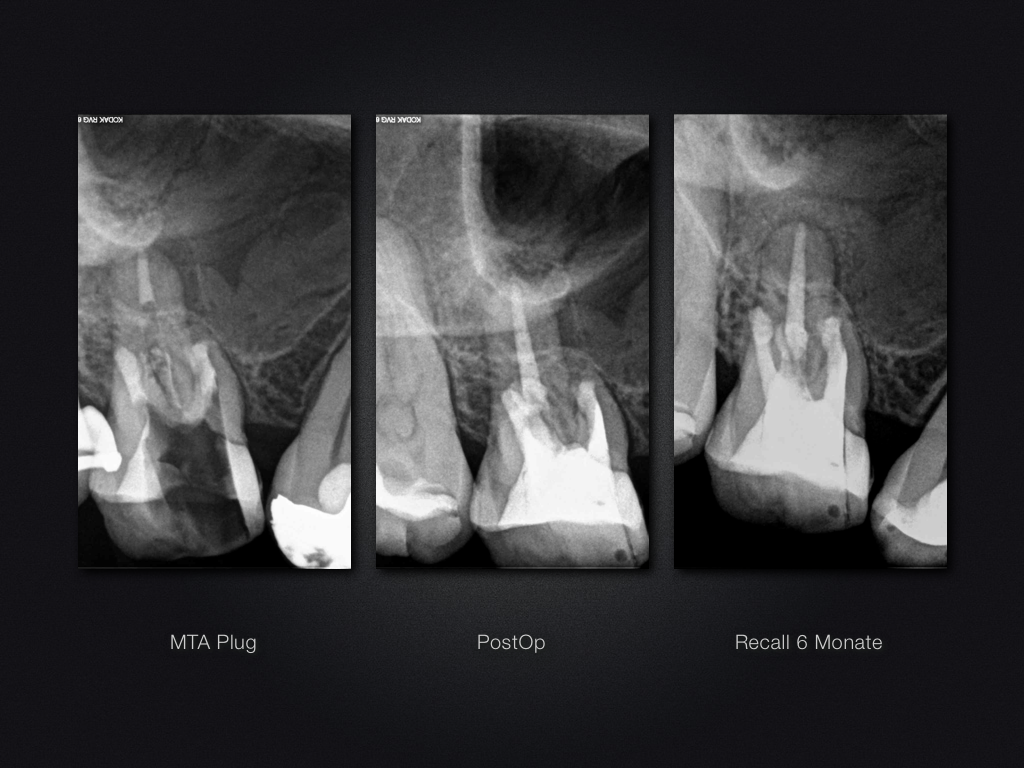

16D.013

Saving Hopeless Teeth (XXX)